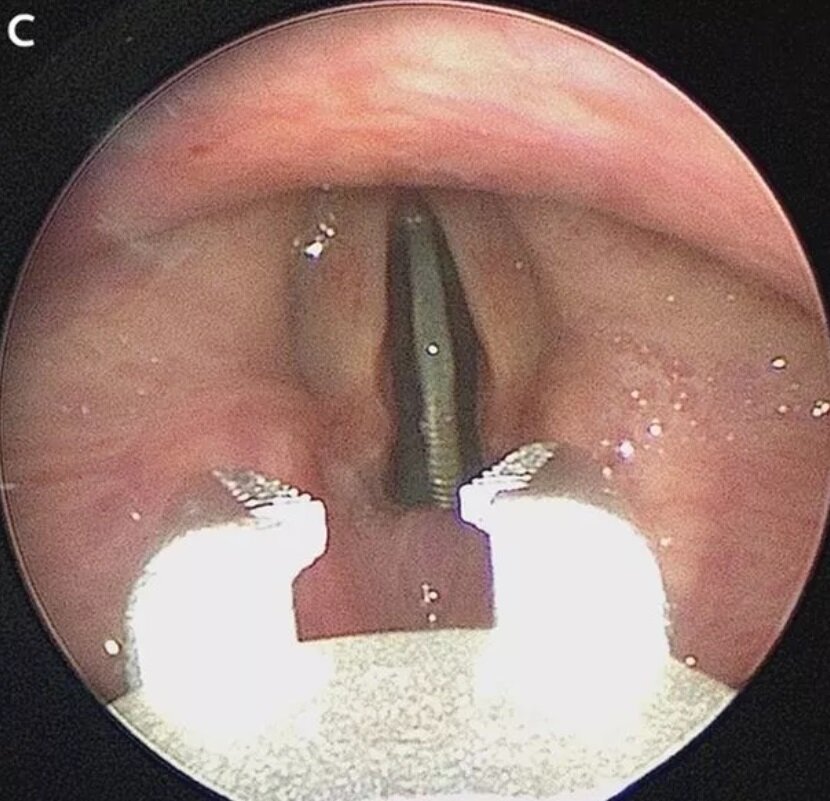

سکه‌ای به‌شکل عمودی، درست مانند دستگاه‌های سکه‌ای، بین تارهای صوتی نوجوان کالیفرنیایی گیر کرده بود و تبدیل به بحثی در نشریات علمی آمریکا شد.

نادیا زکالوند: تیمی از پزشکان اورژانس بیمارستانی در کالیفرنیا دور هم جمع شدند تا بتوانند سکه‌ای را از گلوی نوجوانی خارج کنند که بین تارهای صوتی او گیر کرده بود. این نوجوان به‌طور تصادفی این سکه را قورت داده بود و از آنجایی‌که عمودی در گلوی او قرار گرفته بود، مشکلی در تنفس یا قورت دادن آب دهان او به وجود نیاورده بود.

به گفته پزشکان معالج، وقتی کودکان بزرگتر سکه یا جسمی خارجی قورت می‌دهند، این اجسام به‌لطف جاذبه و اندازه بزرگتر راه‌های هوایی (مجرای تنفسی)، راحت‌تر از بدن خارج می‌شوند. اما سکه‌ای که در گلوی این نوجوان گیر کرده بود، به‌صورت عمودی بود و پزشکان برای خارج کردن آن باید دقت بسیاری می‌کردند.

خوشبختانه پزشکان کالیفرنیایی توانستند سکه را از گلوی نوجوان بدون کوچکترین صدمه به بافت‌های ظریف تارهای صوتی او خارج کنند.